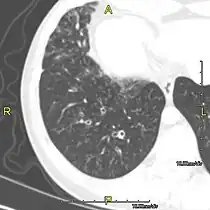

- Sagittal CT image showing "tree in bud" appearance of mucous impaction in distal small airways related to primary ciliary dyskinesia